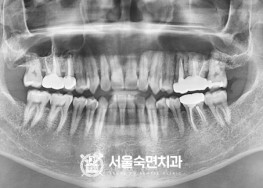

임플란트-치료-전후사진

서울대학교-출신-보건복지부-인증-통합치의학과-전문의-2인-책임관리